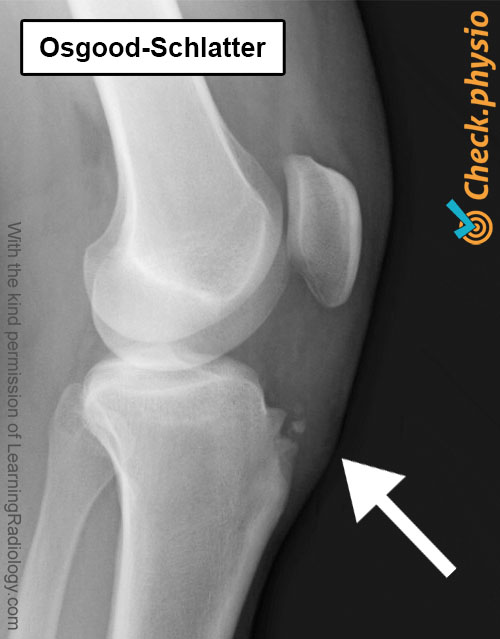

Diagnosen stilles av lege eller fysioterapeut. Det gjennomføres først en samtale for å finne ut hvordan symptomene har oppstått og hvor de kommer fra. Ved den kliniske undersøkelsen testes festet av kneskålens sene på tuberositas tibiae. Dersom det oppstår smerte ved trykk på kulen eller det finnes en fortykkelse, vil mistanken om Osgood-Schlatter raskt oppstå.